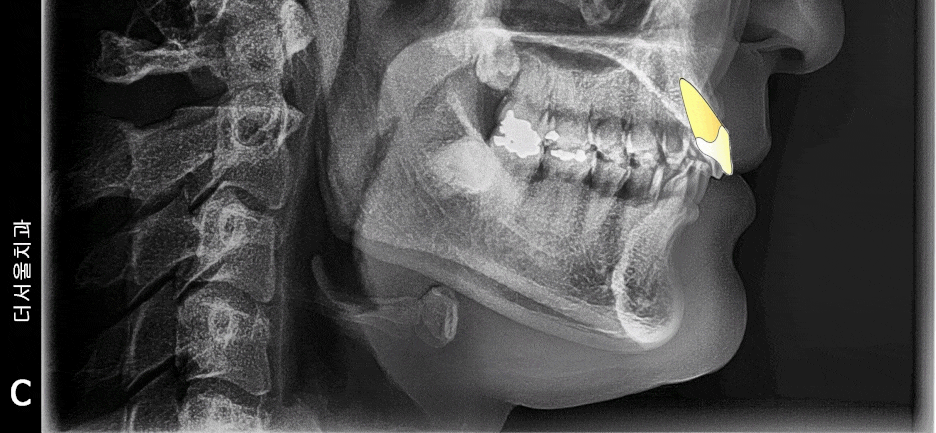

측면에서도 마찬가지로 엑스레이를 찍습니다.

돌출입 또는 무턱의 정도를 알 수 있으며,

코 끝과 턱 끝을 이은 심미선(리케츠라인)을

활용 해서 환자를 어떤 방향으로 끌고 가야

되는지를 알려줄 수 있는 정보입니다.

앞서 보여드린 사진에서,

두부 방사선 측면 사진(Ceph) 이 있었죠?

거기에 가상의 지표를 찍게 됩니다.

cephalometric bony landmark 라 부르는데,

사진으로 보여드리겠습니다.

이렇게, 해부학적 요소에 따라서

랜드마크를 찍어서 발치를 해야 되는지

브라켓은 어디에 붙여야 되는지 등을

알 수 있습니다.

저는 여기서, 코 끝과 턱 끝을 이은

‘심미선’ 이라 부르는 리케츠 라인을 주로 봅니다.

이 선을 기준으로, 입술이 튀어나와있다면

‘돌출입’ 그렇지 않다면 ‘정상’ 의 범주로 보며

발치 결정의 기준점이 될 때도 있습니다.